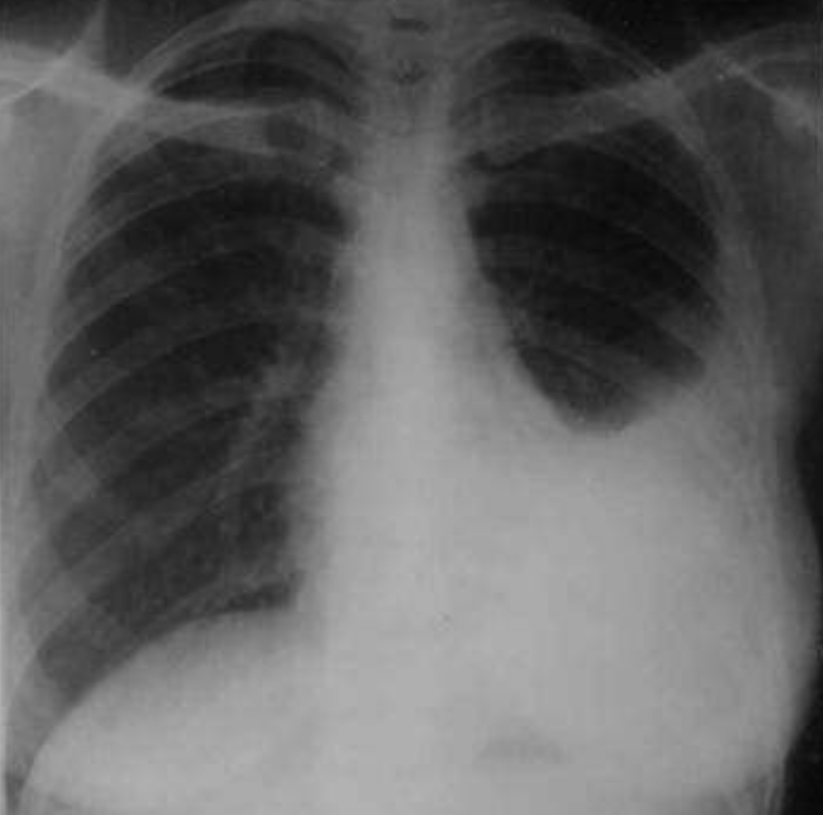

Juru x-ray berserta mesin x-ray mudah alih (portable x-ray) dipanggil.

Hasil keputusan x-ray menunjukkan paru-paru kiri Ali dipenuhi cecair.